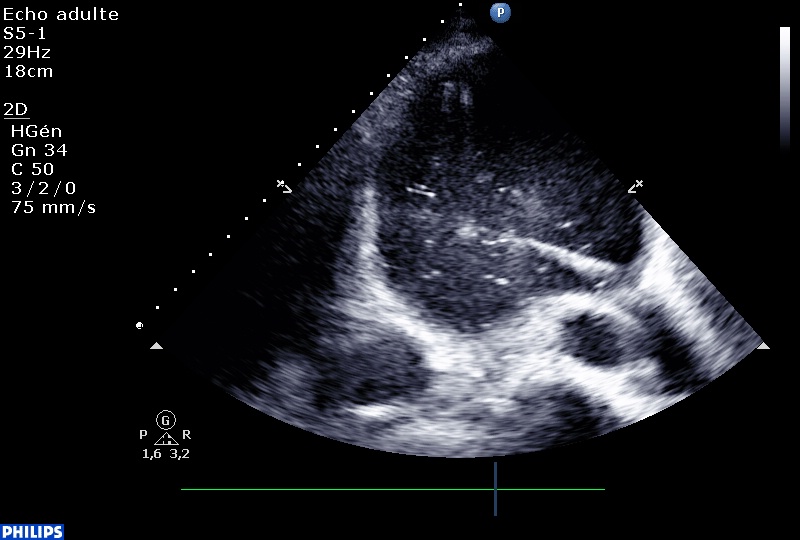

Untitled from fish Nip echocardiographie on Vimeo.

Même si il est difficile de sortir un échographiste de son rôle de contemplateur, c’est possible. Après avoir injecté quelques bulles pour s’assurer d’être dans le péricarde, on passe un guide métallique (pas trop loin le guide, Nico, stp…)

Et on draine. En fin de procédure, on laisse le drain en place pour le liquide restant.